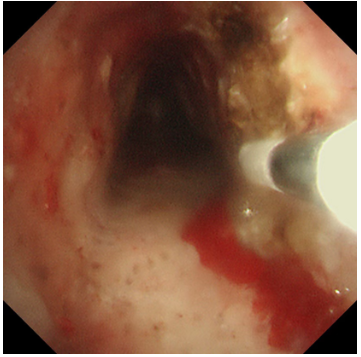

冷凍修復(fù),深度“清創(chuàng)”:隨后,應(yīng)用冷凍探頭對殘余的增生組織及基底進行凍融治療。極低溫的探頭接觸組織,能使其變性、壞死并最終脫落,同時還能有效止血、減少瘢痕形成。這一步驟如同為氣道進行一次深度的“保養(yǎng)與清潔”,能更徹底地清除病灶,降低復(fù)發(fā)風(fēng)險。

兩種技術(shù)優(yōu)勢互補,相得益彰,在微小創(chuàng)傷的前提下,實現(xiàn)了對復(fù)雜氣道狹窄的最大化疏通。